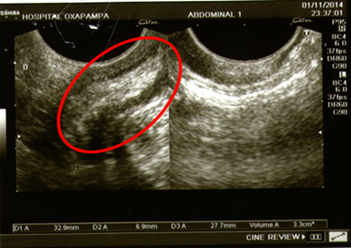

En la hospitalización, luego de aproximadamente 12 horas, se nota quejumbrosa y refiere dolor en flanco derecho, por lo que se decide tomar una ecografía abdominal y transvaginal (Figuras 1 y 2). Donde se llegó a evidenciar: aumento del diámetro apendicular, líquido libre periapendicular e inmovilidad del apéndice.

Según los resultados se presentó: útero grávido, altura uterina 32 cm., situación longitudinal, posición dorso derecho, presentación cefálica. Punto doloroso de Mc Burney (+), Blumberg (+) con el cual se diagnostica abdomen agudo quirúrgico y posible apendicitis aguda complicada, el cual se relaciona estrechamente con sus exámenes de laboratorio.